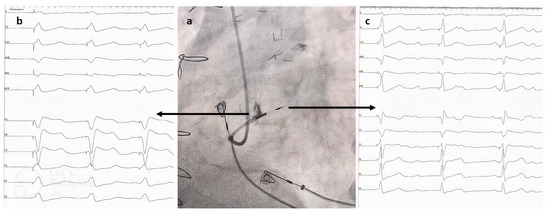

2.3. Pacing Procedure

3.3.1. Depolarization Parameters

3.3.2. Repolarization Parameters